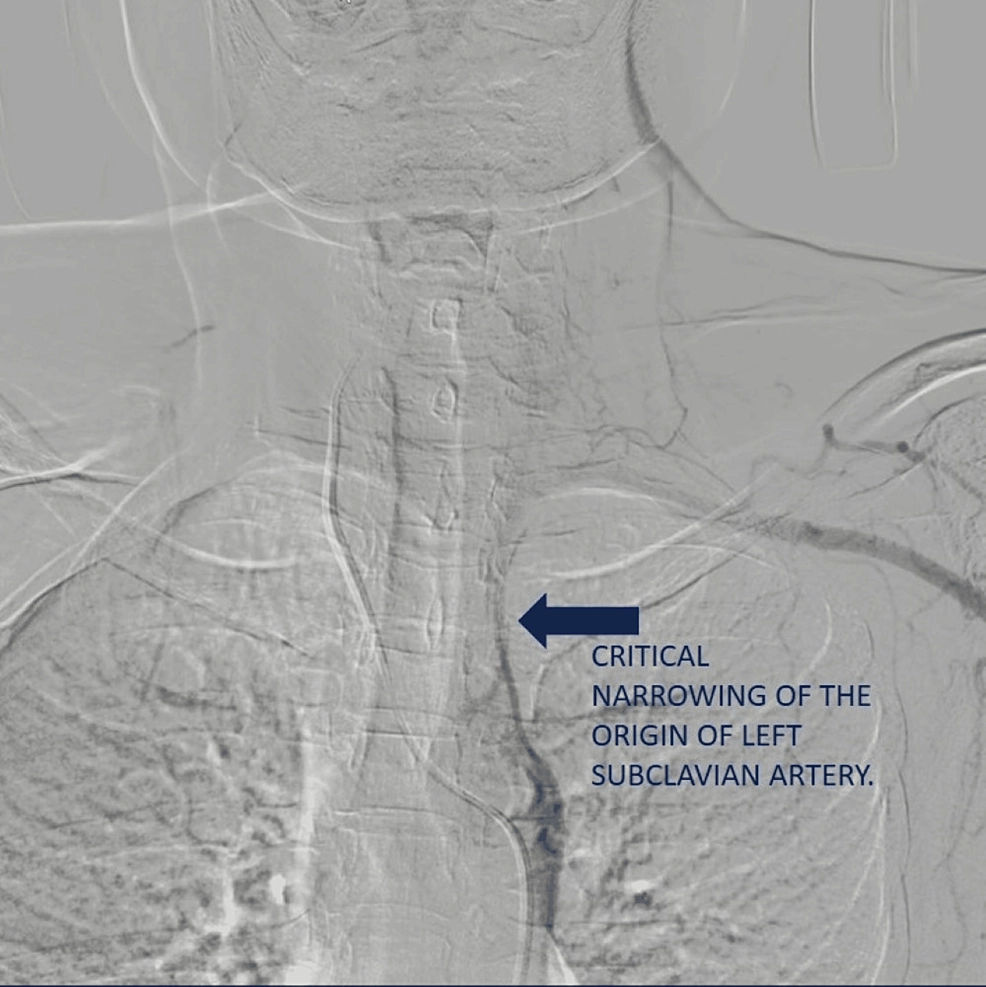

Images visual examples of subclavian steal syndrome

Visual of subclavian steal syndrome often highlight reduced cerebral blood flow and compensatory circulation changes.